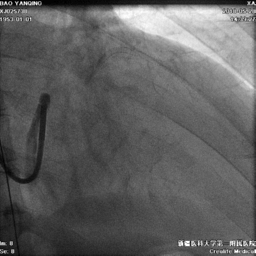

冠状静脉造影

● 冠状静脉造影,选择靶血管侧静脉。血管远端无法看清,使用鞘中鞘造影靶血管

鞘中鞘超选靶血管造影

● 根据造影结果尝试选择侧静脉